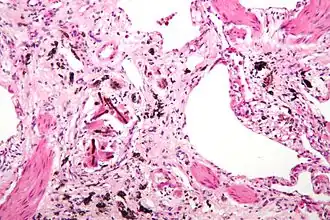

Vroege asbestose

Asbestose is een aandoening die behoort tot de pneumoconioses (stoflongen) waarbij verbindweefseling van de luchtwegen optreedt. De longcapaciteit neemt af, waardoor zich overbelasting van het hart kan voordoen. Asbestose wordt veroorzaakt door blootstelling aan asbest. Asbestose is een erkende beroepsziekte, maar men kan op veel manieren met asbest in aanraking komen omdat het in het verleden op zeer veel plaatsen is verwerkt.

Asbestose is een diffuse longfibrose waarvan de diagnose steunt op de radiografie, de CT-scan en/of de histologische bevindingen, samen met een gecumuleerde blootstelling en/of een longbelasting met asbestvezels of asbestlichaampjes die overeenstemt met de diagnose. De CT-scan toont septale en niet-septale lijnen en honingraat-beelden. De radiografische diagnose steunt op de aanwezigheid van kleine onregelmatige opaciteiten (s, t, u), stadium $ 1/1 volgens de classificatie van de Internationale Arbeidsorganisatie. Asbestose uit zich functioneel in de vorm van een vermindering van de totale longcapaciteit, de vitale capaciteit en/of een vermindering van de diffusiecapaciteit. Bij minimale vormen van asbestose zijn er niet altijd longfunctiestoornissen aanwezig.